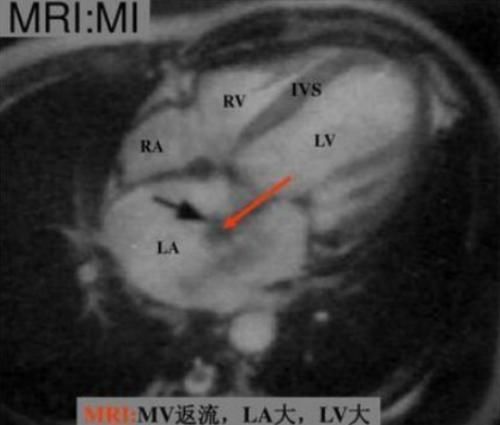

在达芬奇流传后世的众多手稿中,有学者注意到了一幅绘制心脏结构的解剖图,图中还明显地将心肌小梁给画了出来。前段时间欧洲分子生物学实验室在《自然》期刊上发表了一篇关于心脏结构最新认知的论文,研究人员通过研究和分析2.5万张磁共振的心脏图像,发现心肌小梁或许还有更多功能。

简而言之,心肌小梁这个机构在以往的医学研究中并未得到重视,因此它的潜在功能也一直未被发现。直到欧洲分子生物学实验室的研究人员对来自英国生物样本库的2.5万张心脏磁共振图像进行研究,才进一步认识了心肌小梁的生理作用。研究人员发现,心肌小梁的存在使得血液在流动的时候受到更多的阻力。